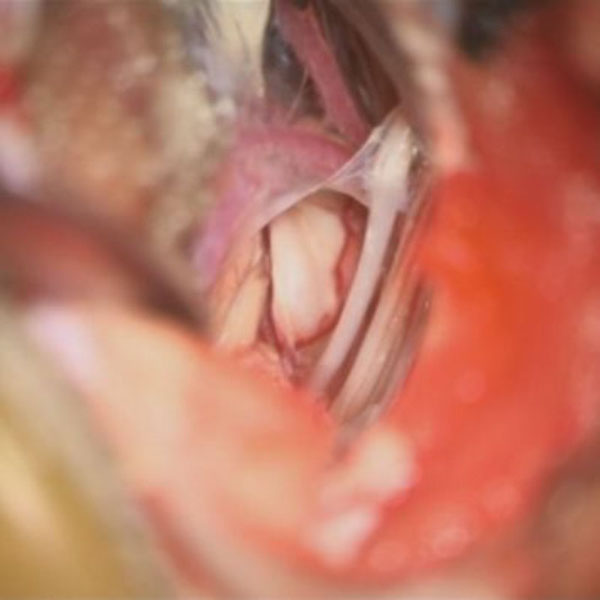

手術中

処置前

処置後